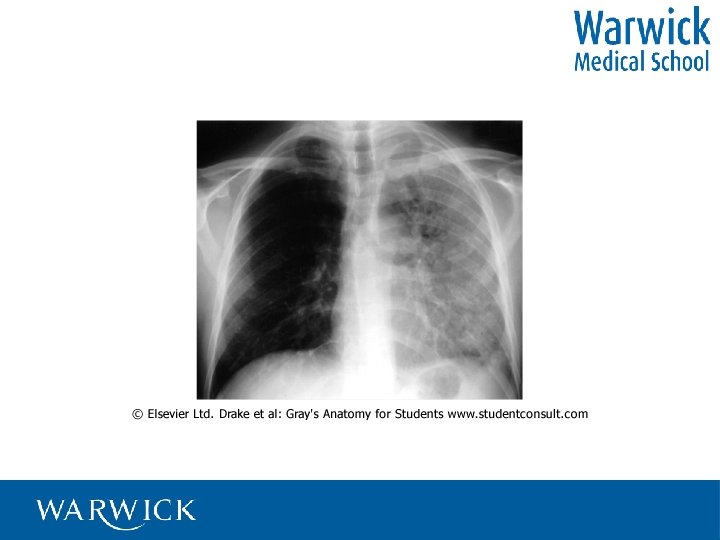

Where do you listen? Over the lungs! Other structures may interfere • Superficial –

Where do you listen? Over the lungs! Other structures may interfere • Superficial – breast, fat, scapulae • Underlying - liver, heart